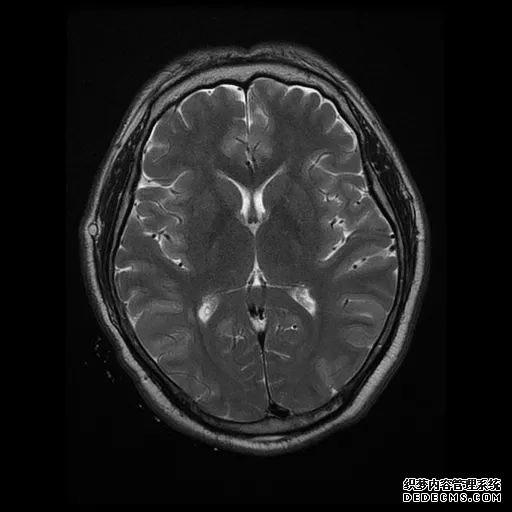

脑MRI显示尾状核、扁豆状核和脑梗头部T2/FLAIR呈双侧对称异常高信号。扩散限制涉及这些区域,其特征是扩散加权DWI(B-1000)上的高强度,ADC图上相应的减弱强度。

印象:通过将这些成像模式与临床和实验室检查结果相结合,就有可能得出低血糖性脑病。

影像影响内囊后肢、大脑皮层(特别是枕叶和岛叶)、海马和基底节区,常是双边对称性的。